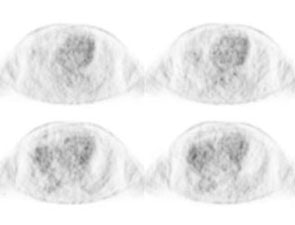

PET: Studies indicate that round atelectasis is not metabolically active on FDG-PET imaging [7].

Round atelectasis on PET FDG imaging: The images below demonstrate the typical CT and FDG PET findings in round atelectasis. On CT, there are thickened lung markings and vessels which swirl into the lesion that abuts an area of pleural thickening. Note the lack of metabolic activity in round atelectasis on PET imaging. |